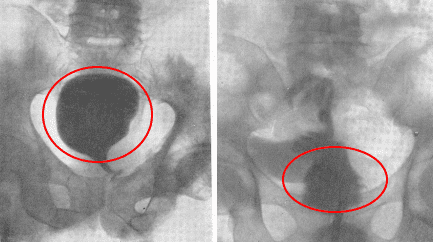

أستطيع أن أرى الرجال الذين يزورونني بسبب التهاب البروستاتا أو تضخم البروستاتا الحميد كل يوم. في الواقع، هذه الأمراض هي حالات ما قبل سرطانية غدة البروستاتا.

كما ترى، ترتبط هذه المشكلات ارتباطًا مباشرًا بممارسة الجنس بانتظام. عندما يتوقف الرجل عن ممارسة الجنس بانتظام، تصاب غدة البروستاتا بالاحتقان، ونتيجة لذلك، يتسبب ذلك في حدوث التهاب ويوقف إنتاج الهرمونات المهمة. بدون علاج طويل الأمد، يتطور التهاب البروستاتا إلى تضخم البروستاتا الحميد الذي يتحول بعد ذلك إلى سرطان.

سرطان البروستاتا ناتج عن عدم ممارسة الجنس لفترة طويلة. توفي رجل 60 سنة.